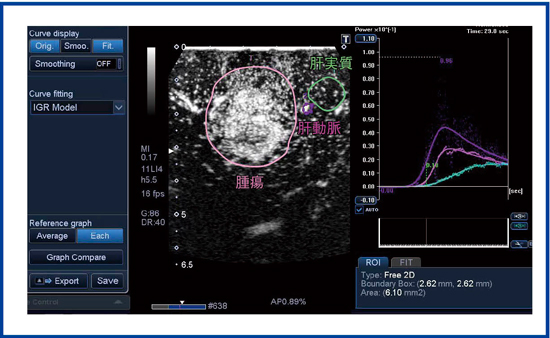

TICフィッティングによる客観化については,ピーク値(PI),立ち上がりからピークまでの時間(TPI),平均通過時間(MTT),傾き(Slope),AUCなどさまざまなパラメータがあるが,フィッティングカーブを簡便に描けるようになり,血流の解析が容易になった(図4)。解析手順は,(1) Rawデータを選択,(2) ROIを設定,(3) 自動ROIトラッキング,(4) フィッティングでパラメータ算出,という流れである。これまでは機器外にデータを出して解析していたが,TICフィッティング機能で簡便になり,解析時間の短縮が期待される。

図5の症例は,肝細胞がん(70歳代前半,男性)。大きな腫瘍に流入する血流について,TIC解析を行うことが可能である。TIC解析結果は,肝細胞がんや転移性肝がんの鑑別などに有用と考える。

図4 パラメータ解析,フィッティングにより客観化でき,分子標的薬の早期効果判定などに応用される。

図5 肝細胞がん(中分化型)のTIC解析